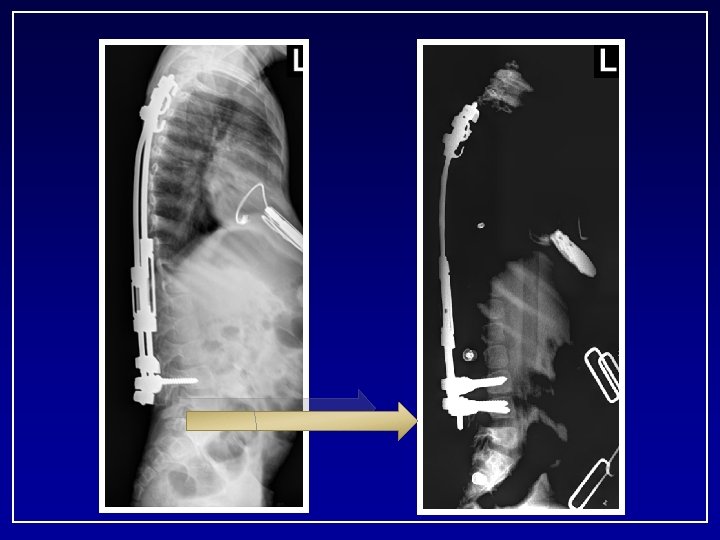

57 months after initial surgery 38 CC Age 7+3 Cobb: Pre 86° FU 38° T 1 -S 1: Pre 211 mm Post 247 mm FU 301 mm Total 9. 0 cm Length. 9

April 2008 • • Exploration of fusion Removal Implants New Implants Revision T 3 -T 5

9. 3. 2008 - 7 years post op • T 9 -L 3 40 deg • T 2 -T 9 45 deg Kyphosis • T 3 -T 12 48 deg • T 12 -S 1 42 deg Growth T 1 -S 1 Pre: 211 cm Post: 247 cm FU: 338 cm Total lengh: 12. 7 cm Expected growth: 9 cm # lengthening: 13